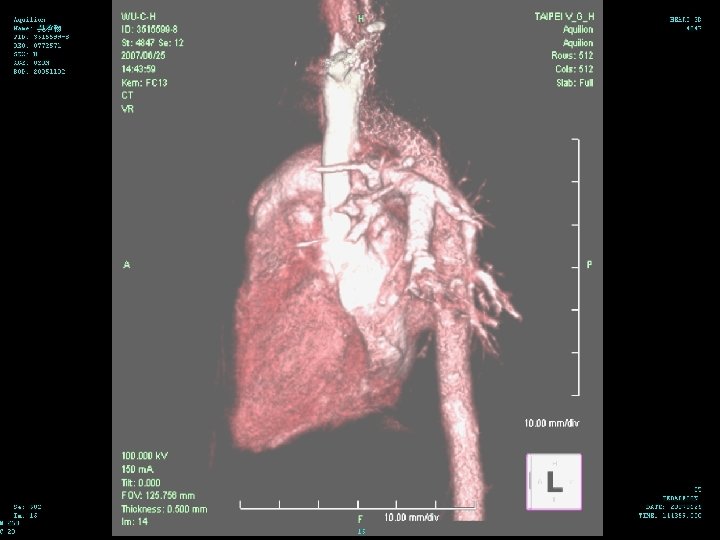

Hospital Course (6/25 -28) 3 D CT of chest performed on 6/25 n There is narrowing of the trachea in the level of aortic arch with narrowest diameter about 0. 25 cm about 1. 2 cm in length n There is dextrocardia with left side aortic arch n There is double SVC with left SVC drainage to coronary sinus n

Diagnosis identification of a right aortic arch on chest radiograph n An ill-defined arch location is often observed in patients with double aortic arch n compression of the trachea and hyperinflation and/or atelectasis of some of the lobes of either lung n chest radiography is not very sensitive n

Diagnosis CT/MRI/Angio:These expensive radiological studies are rarely necessary to evaluate vascular rings n Although these modalities provide excellent delineation of all of the associated structures, they should be reserved for cases in which the results of barium esophagram do not provide a clear diagnosis n